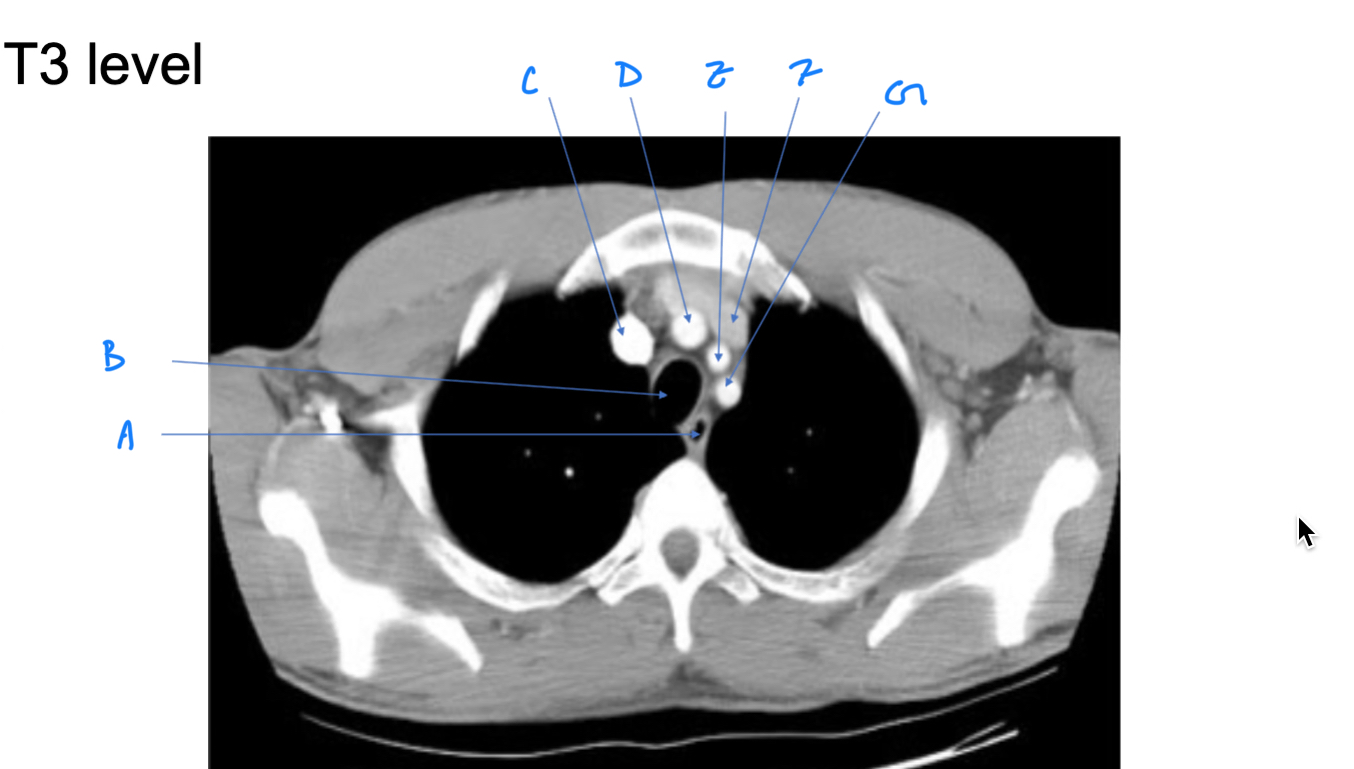

Esophagus

A. Identify

Trachea

B. Identify

R Brachiocephalic v.

C. Identify

Brachiocephalic trunk

D. Identify

L CCA

E. Identify

L Brachiocephalic v.

F. Identify

L Subclavian a.

G. Identify

Trachea

A. Identify

Superior vena cava (SVC)

B. Identify

Arch of aorta

C. Identify

Esophagus

D. Identify